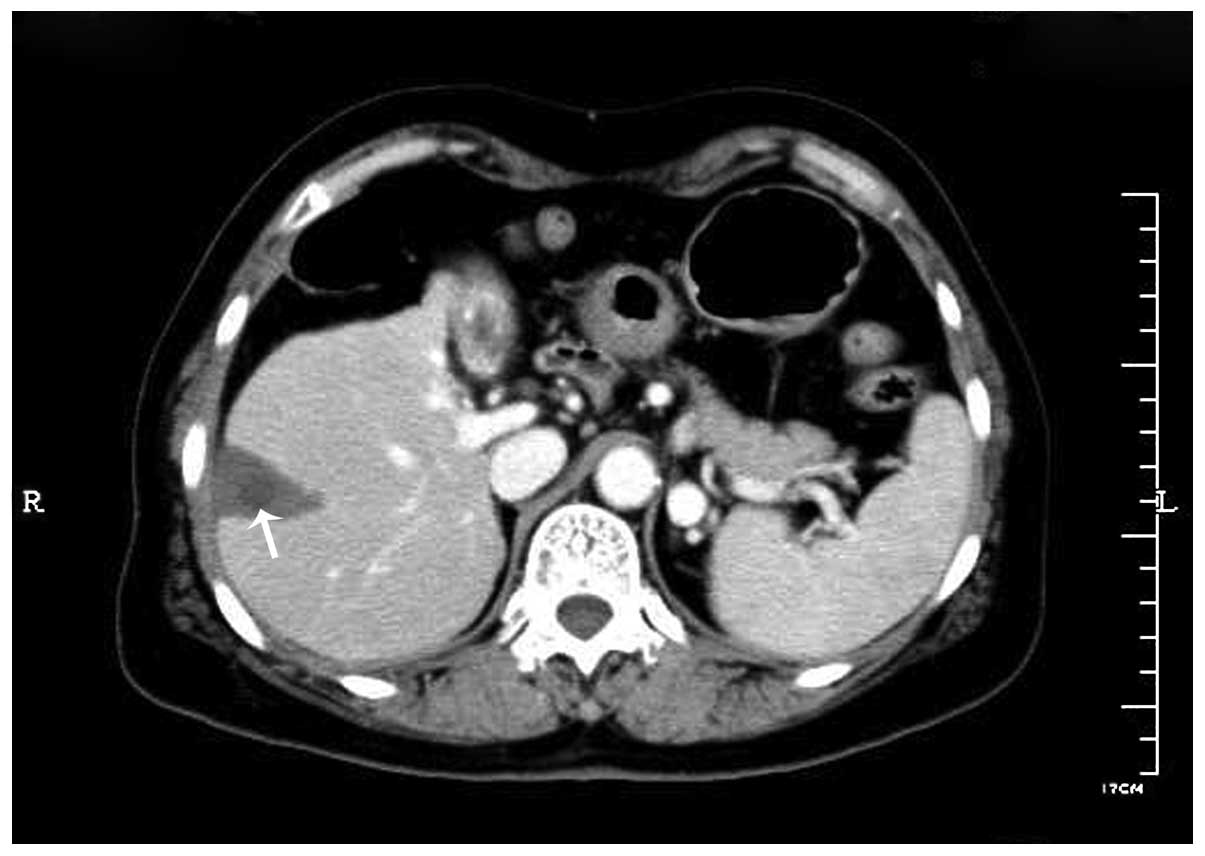

Diaphragmatic perforation with colonic herniation due to hepatic radiofrequency ablation: A case report and review of the literature

Radiofrequency ablation (RFA) has been widely accepted as an alternative treatment for unresectable primary and metastatic hepatic tumors, with satisfactory rates of local response and significant improvements in rates of overall survival. Numerous large series studies have shown that RFA is safe and effective, with a low mortality rate and a low major complication rate. Major complications, including diaphragmatic perforation and hernia, have rarely been previously reported. The current case report presents a case of diaphragmatic hernia with perforation of the incarcerated colon in the thoracic cavity 12 months following hepatic RFA, and reviews nine previously reported cases of diaphragmatic hernia. Comprehensive analysis of the nine cases demonstrated possibilities leading to diaphragmatic hernia following diaphragmatic thermal injury as a consequence of hepatic RFA. Clinicians and radiologists must consider diaphragmatic thermal damage following hepatic RFA for liver tumors adjacent to the diaphragm, particularly for patients with symptoms of ileus, dyspnea, chest pain, pleural effusion and right shoulder pain.

Figure 1